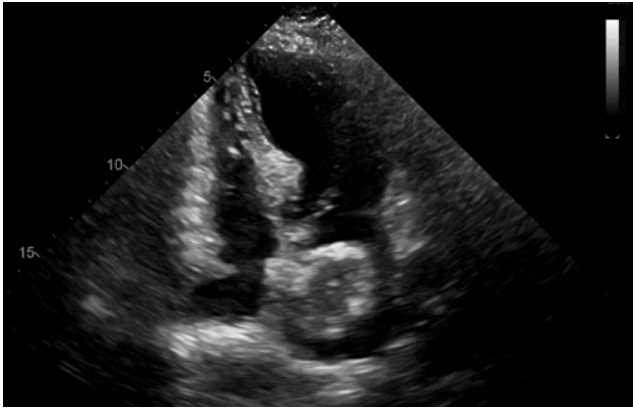

Paciente de 42 anos de idade, sexo feminino, relata há alguns meses perda ponderal, fadiga, mal-estar. Há dois meses refere episódios de síncope e dispneia aos moderados esforços. A paciente realizou ecocardiograma transtorácico com a imagem abaixo. Com base nessa situação hipotética, de acordo com a história clínica, epidemiologia e achado ecocardiográfico, o diagnóstico mais provável é

Imagem: arquivo pessoal.